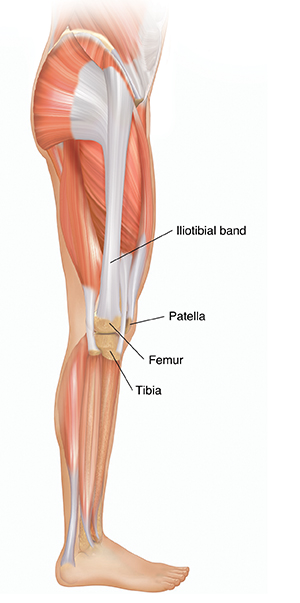

Understanding Iliotibial Band Syndrome Saint Luke s Health System

Diagnosing Lateral Thigh Pain IT band syndrome Hip Bursitis and

Product Name: Muscle on outside of clearance thighMuscle Strains in the Thigh Florida Orthopaedic Institute clearance, Lateral leg pain more than just the IT Band Revo Physiotherapy clearance, 6 Power Packed Outer Thigh Exercises For Lower Body Strength DMoose clearance, 10 Best Thigh Exercises For Leg Day Workouts Steel Supplements clearance, Diagnosing Lateral Thigh Pain IT band syndrome Hip Bursitis and clearance, Can Rolling Your IT Band Make It Worse Functional Performance clearance, Thigh muscles side view Human anatomy Leg anatomy Human muscle clearance, Quad Muscles Function and Anatomy clearance, Rolling of the IT band anatomy of outer thigh muscles blog post clearance, Vivian Grisogono ABOUT THE FRONT THIGH MUSCLES clearance, Iliotibial band syndrome ITBS clearance, Adductor muscles of the hip Wikipedia clearance, The Secret to Resolving IT Band Syndrome using Thai Massage Thai clearance, Professor Ernest Schilders The London Hip Arthroscopy Centre clearance, Muscles of the Posterior Thigh Hamstrings Damage TeachMeAnatomy clearance, Runners Knee also known as ITB Syndrome Do You Have It and How clearance, The Physio Detective The ITB 5 things you probably haven t clearance, Diagnosing Lateral Thigh Pain IT band syndrome Hip Bursitis and clearance, Vivian Grisogono ABOUT THE FRONT THIGH MUSCLES clearance, Anatomy Of Human Thigh Muscles Greeting Card clearance, Muscles of the Human Body clearance, Understanding Iliotibial Band Syndrome Saint Luke s Health System clearance, Diagnosing Lateral Thigh Pain IT band syndrome Hip Bursitis and clearance, Meralgia paresthetica Symptoms and causes Mayo Clinic clearance, Foam rolling IT band Dos and don ts clearance, What is the Vastus Lateralis Muscle Orchard Health Clinic clearance, What is the muscle on the back of your thigh Quora clearance, IT band Friction Syndrome Ortho Rhode Island clearance, Why does the top of my left thigh ache when raising it up Quora clearance, Anatomy of Leg Muscles Plus How to Make the Most of Leg Exercises clearance, Meralgia Paresthetica Neuromuscular and Electrodiagnostic Clinic clearance, Soft Tissue Reconstruction of the Lateral Thigh and Hip SpringerLink clearance, Why Is Your Thigh In Pain 6 Common Causes Carex clearance, Anatomy of the Hamstring Upper Leg clearance, Muscle Knots in Side of Leg IT Band Tiger Tail USA clearance, Front Thigh Pain Anterior Thigh Pain Symptoms Causes Treatment clearance, Pelvic hip and thigh muscles of the right side of the body Part clearance, Outer Quad Exercises 7 Must Do Exercises Fitbod clearance, The Hip Abductor Muscles Trochanteric Bursa and Lateral Outside clearance, Muscles of the hips and thighs Human Anatomy and Physiology Lab clearance, Anatomy of the Piriformis Muscle Spine health clearance, Why Does The Outside Of My Hip Hurt What to Do About It clearance, Vastus lateralis muscle Wikipedia clearance, What is IT Band Syndrome and How Can I Fix It clearance, IONA Physiotherapy WHAT AND WHERE IS THE ILIOTIBIAL BAND ITB clearance, Groin Strain Symptoms Causes Treatment Rehabilitation Exercises clearance, Simple Ways to Stretch Your Outer Thighs 9 Steps with Pictures clearance, Meralgia Paresthetica Causes Symptoms Treatment clearance, Knee Muscles Anatomy Function Injuries Knee Pain Explained clearance, How to Cure Thigh Muscle Pain clearance.